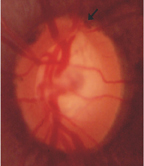

青光眼造成的傷害是無法回復的,如何減少青光眼的傷害是一個重要的課題,「早期發現、早期治療」是對付青光眼的主要策略。由於大部份的青光眼是沒有症狀的,所以「定期追蹤檢查」是發現青光眼的重要方法,四十歲以上的成人每年應至少作一次篩檢,有前述危險因子者更應每半年作一次篩檢。檢查的項目包括眼壓及視神經(眼底)(如:圖二),檢查結果異常者, 要進一步作視野檢查。視神經盤的檢查是目前已知最可靠診斷出青光眼的方法,可藉由眼底鏡來檢查視神經盤與視神經纖維層,惟必須有足夠的經驗才能判定結果。傳統的視野檢查雖然無法早期診斷出青光眼,但可用來確定青光眼的診斷以及追蹤青光眼的控制療效,所以仍是不可或缺的重要檢查。

圖二 青光眼的視神經盤